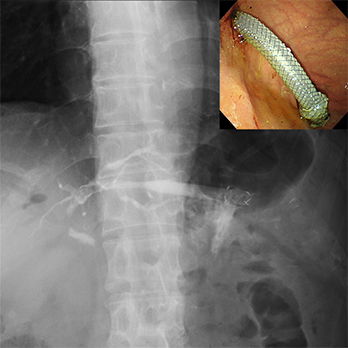

胆管狭窄・膵管狭窄・悪性胃十二指腸狭窄に対する内視鏡的拡張術・ステント留置術

悪性遠位胆管・十二指腸狭窄に対する

内視鏡的メタルステント留置術